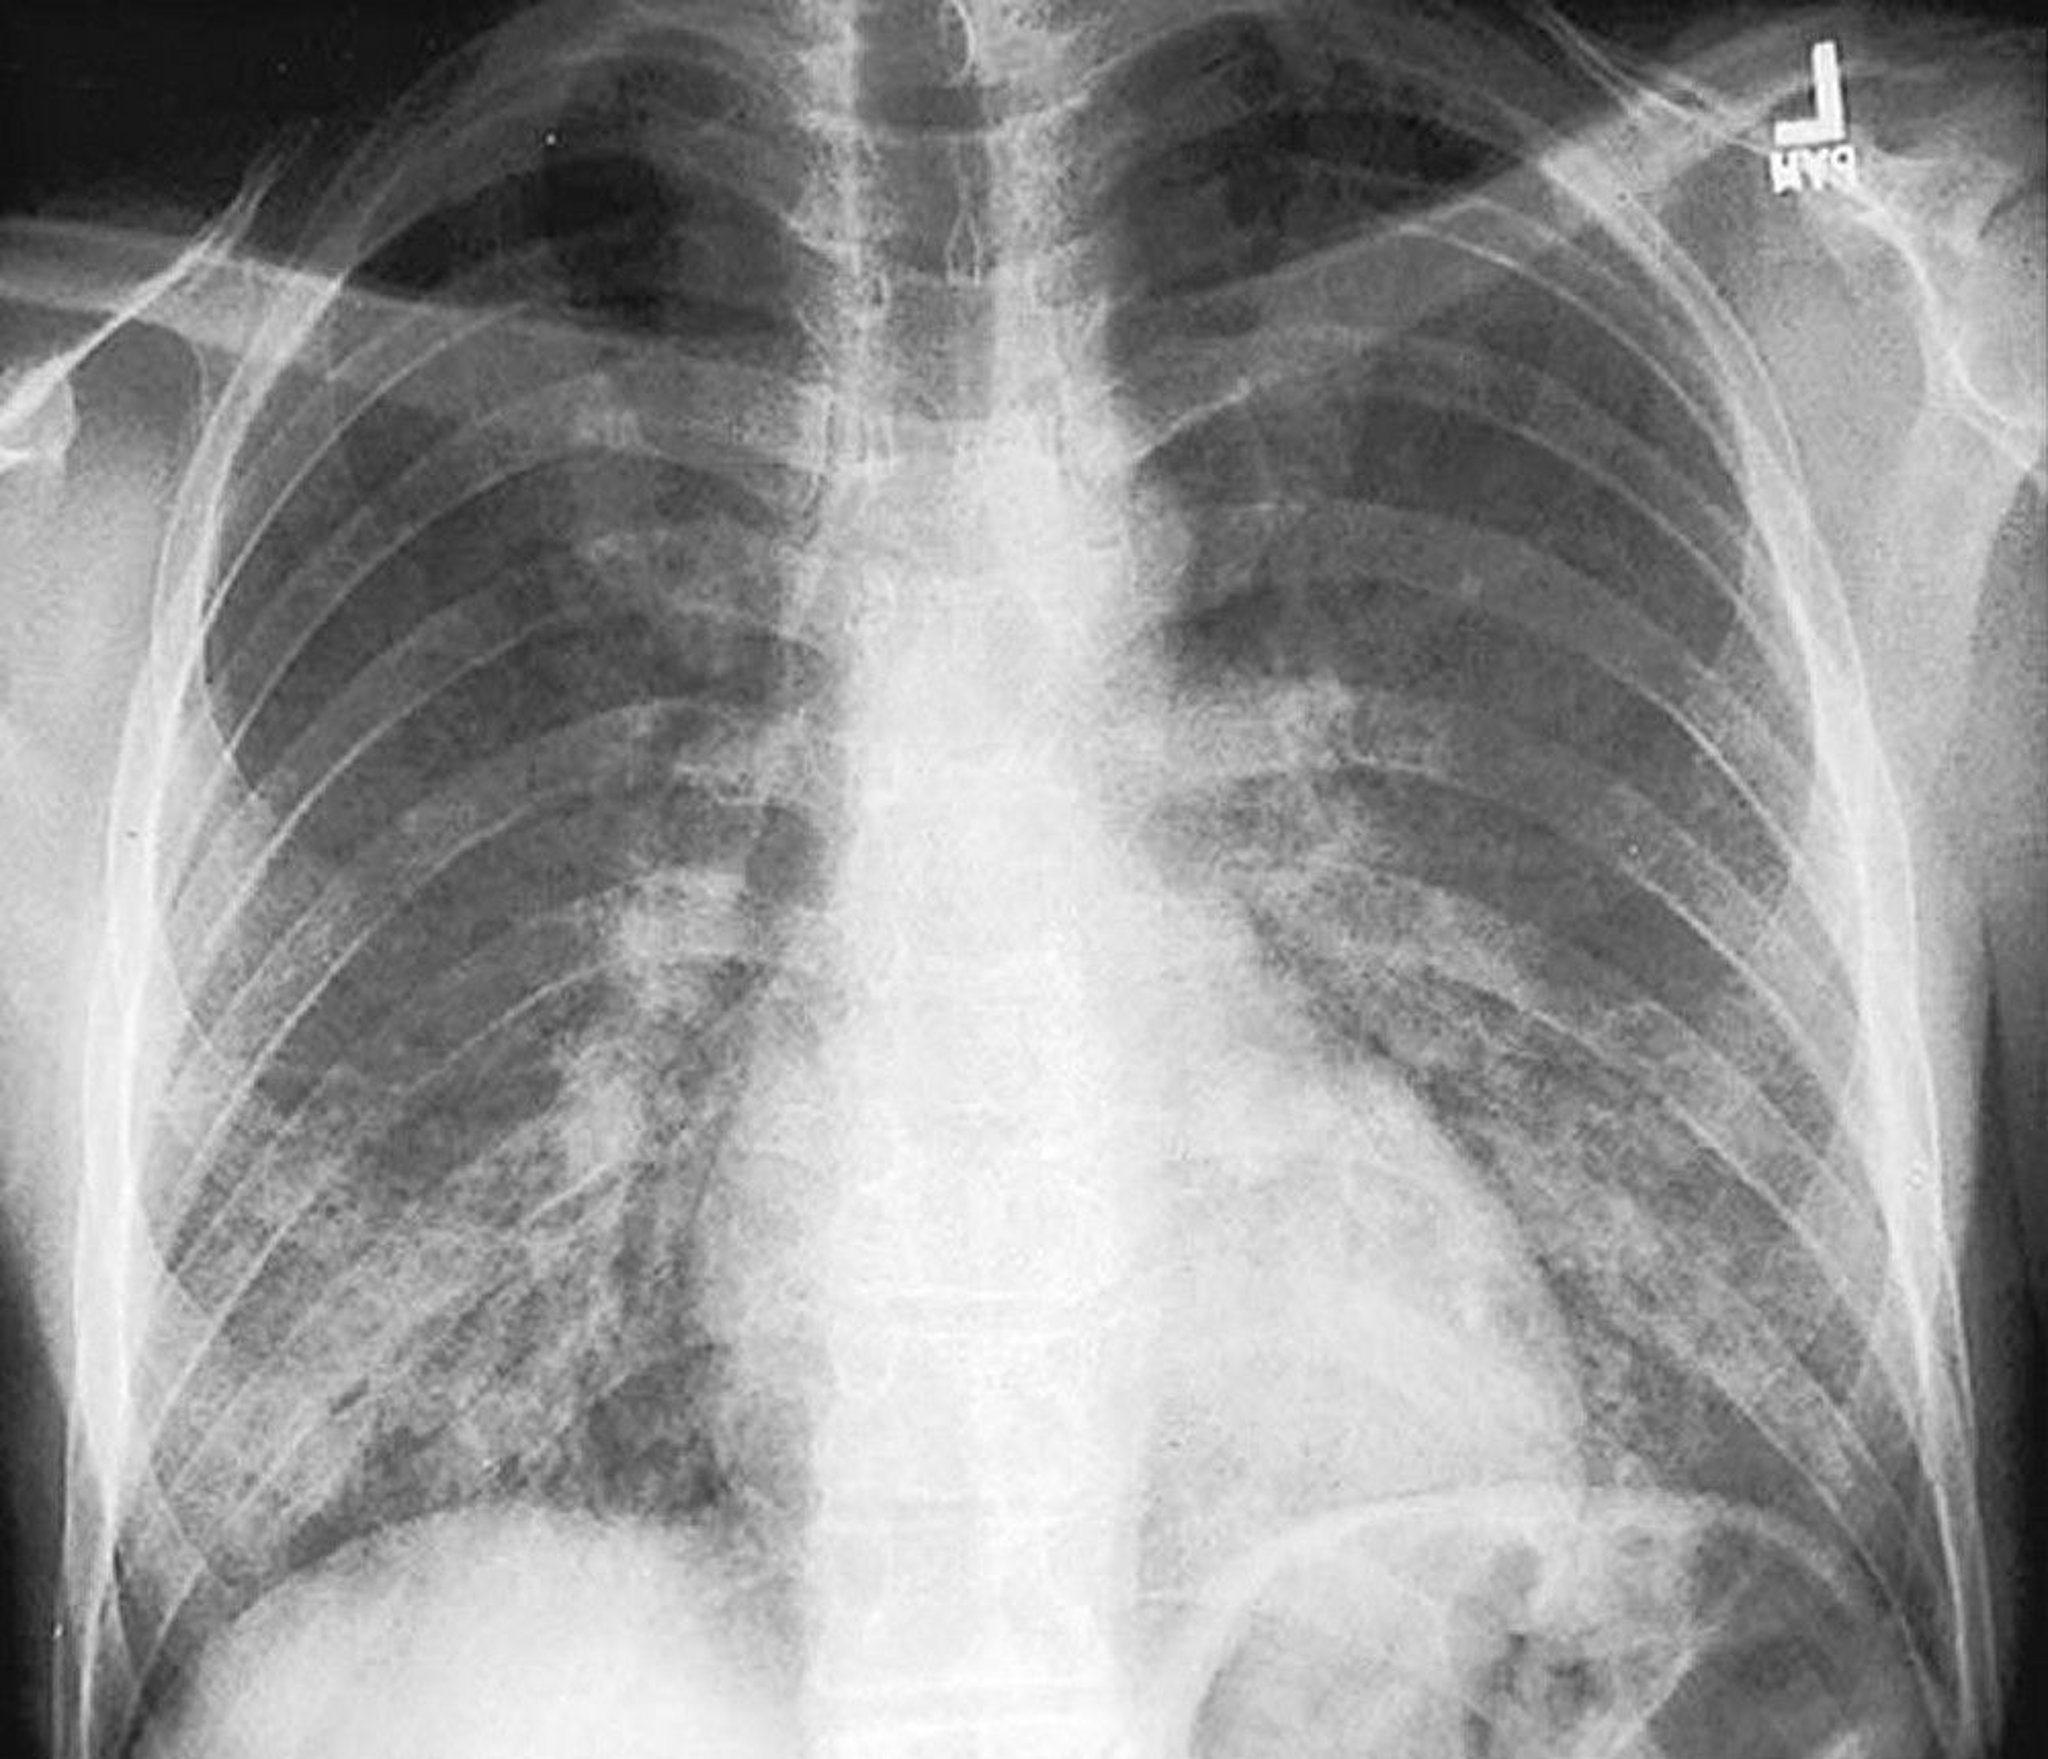

Chest x-ray of an HIV-infected patient with Pneumocystispneumonia, revealing characteristic bilateral, diffuse, granular opacities.

By permission of the publisher. From Huang L, Piliero P. In Bone's Atlas of Pulmonary and Critical Care Medicine. Edited by J Crapo. Philadelphia, Current Medicine, 2005.